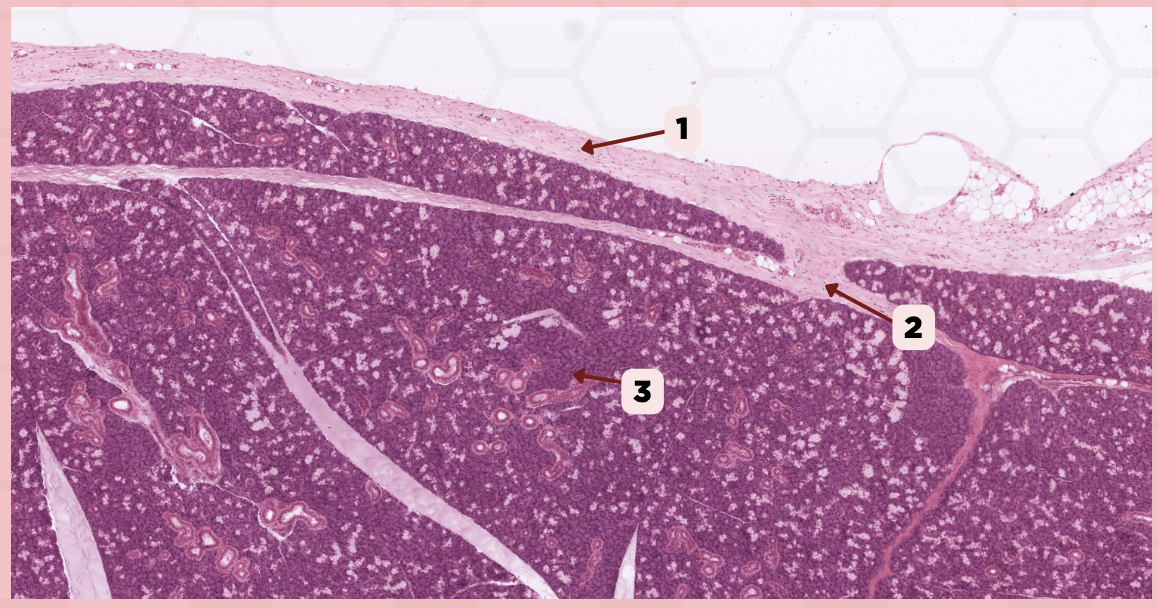

Submandibular

Identify the specimen.

Capsule

Identify the structure labeled as 1.

Septa

Identify the structure labeled as 2.